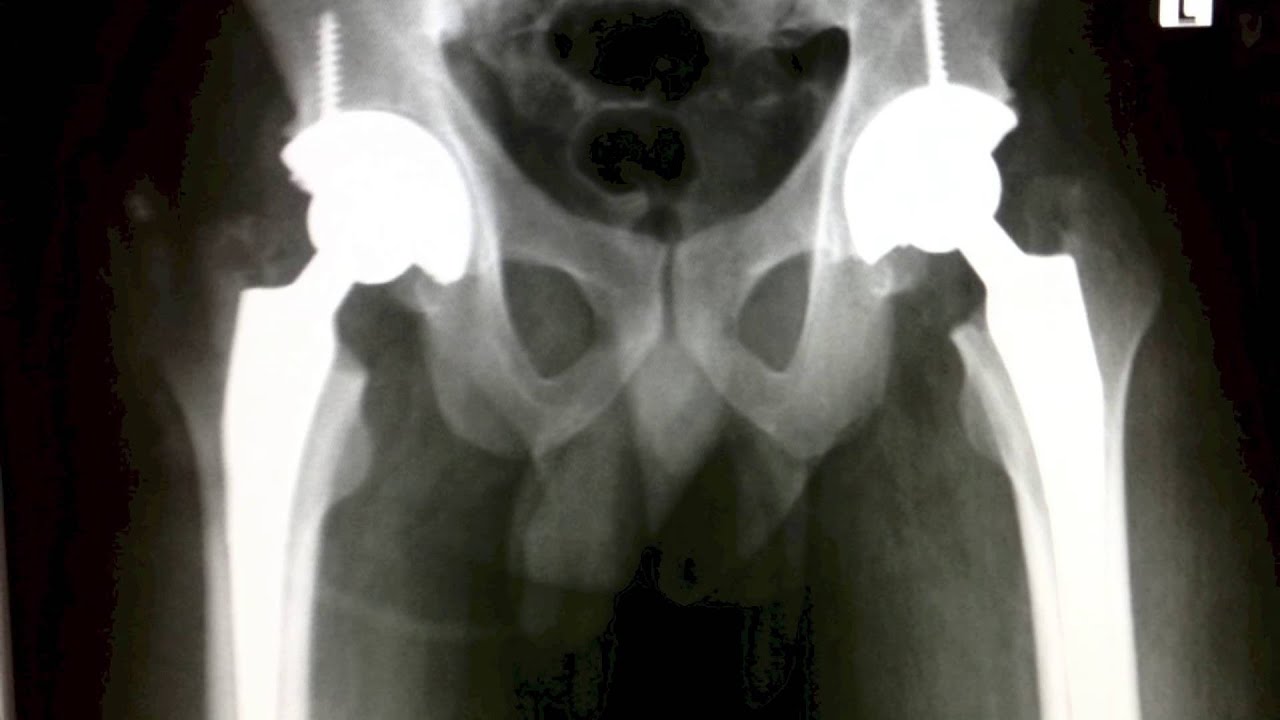

AVASCULAR NECROSIS OF HIPS TOTAL HIP REPLACEMENT BOTH SIDES YouTube

AVASCULAR NECROSIS OF HIPS TOTAL HIP REPLACEMENT BOTH SIDES YouTube What Is Avascular Necrosis Of Right Hip It can lead to joint pain, especially in the hip and knee, and may require surgery to. It causes pain, stiffness, and joint collapse due to blood supply interruption. Bone marrow aspirate and concentration is a newer procedure that might help avascular necrosis of the hip in early. Avascular necrosis is a bone condition that affects the hip, knee, and. What Is Avascular Necrosis Of Right Hip.